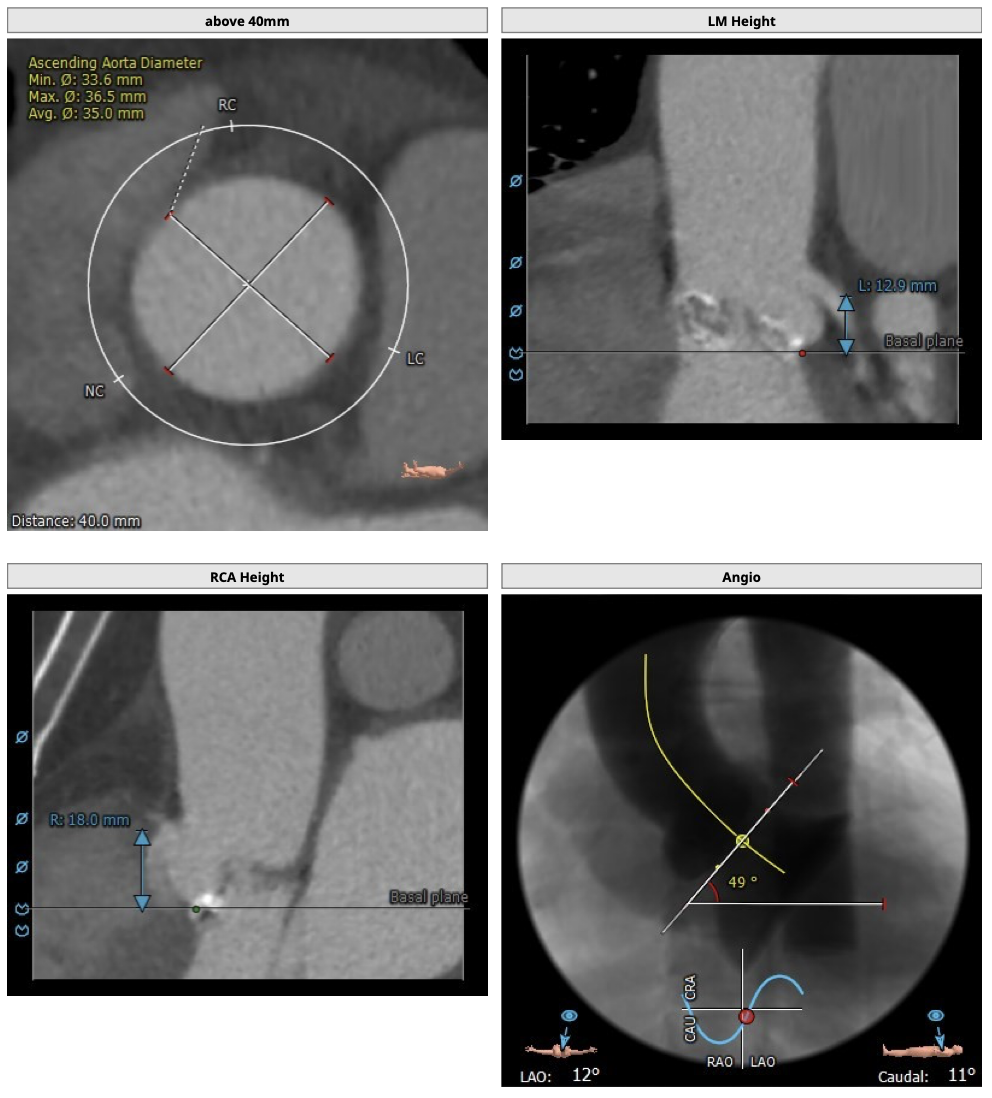

主动脉CT

患者为三叶瓣,轻度钙化,右无、左右疑似部分融合,左冠高度可,右冠高度高,法式窦结构大,左室大,升主动脉未见明显扩张,右股动脉可作为主入路。

经分析研判,根据患者的瓣环径,结合患者瓣上结构,优先选用L26号的VenusA-Valve瓣膜,备L29,使用22mm球囊预扩,根据球扩情况进一步确认选瓣,瓣膜释放后结合造影和超声情况,决定是否后扩。